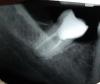

alexmzh Опубликовано 5 мая, 2011 Поделиться Опубликовано 5 мая, 2011 Здравствуйте, был обширный кариес на зубе. Пошел лечить, ставили мышьяк (пасту), стоял 3 дня, затем удалили нерв, после этого чистили каналы и ставили лечебную пасту - все было хорошо, зуб не болел. Поставили постоянную пломбу в итоге, зуб не беспокоил 3 недели - не болел и жевать на нем было не больно. Несколько дней назад, возникла эпизодическая боль (ноющая, кратковременная) в данном зубе (думал показалось). Затем появился дискомфорт при надавливании на внутреннюю стенку зуба и при жевании (не сказать чтоб было больно, но нерпиятно). Затем через день присоеденилась ноющая боль (временами), на следующий день приступы боли участились (ноющая, нудная боль). Сходил в больницу - сделал снимок, хотел бы спросить у вас - из-за чего разболелся зуб (как раз до этого долго находился на улице, замерз - но простуды нет, чувствую себя в целом нормально). Оцените качество пломбировки каналов и скажите нет ли воспалительных процессов в данном зубе и вокруг него. Спасибо, оч.жду ответа. Собираюсь через 10 дней поехать в другую страну (на 2 недели), очень переживаю по поводу данного зуба. Ссылка на комментарий

juli63 Опубликовано 5 мая, 2011 Поделиться Опубликовано 5 мая, 2011 Оцените качество пломбировки каналов и скажите нет ли воспалительных процессов в данном зубе и вокруг него по снимку- каналы до нужного размера не расширены, а соответственно недомыты.боль в зубе появляется- 1.сама по себе, 2.при накусывании или 3.после накусывания когда разжимаете челюсти? Ссылка на комментарий